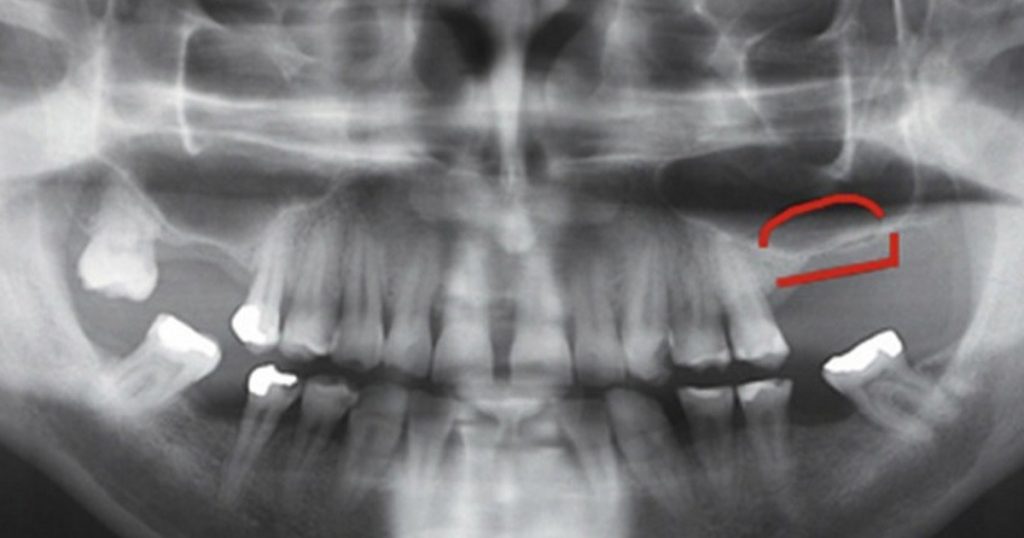

Treatment planning begins with conebeam computed tomography (CBCT) to measure residual bone height (RBH) and evaluate sinus anatomy. A commonly used classification divides cases into three groups:

Residual bone height is not the only factor. Sinus membrane thickness, presence of septa, and access to multiple implant sites also influence technique selection.